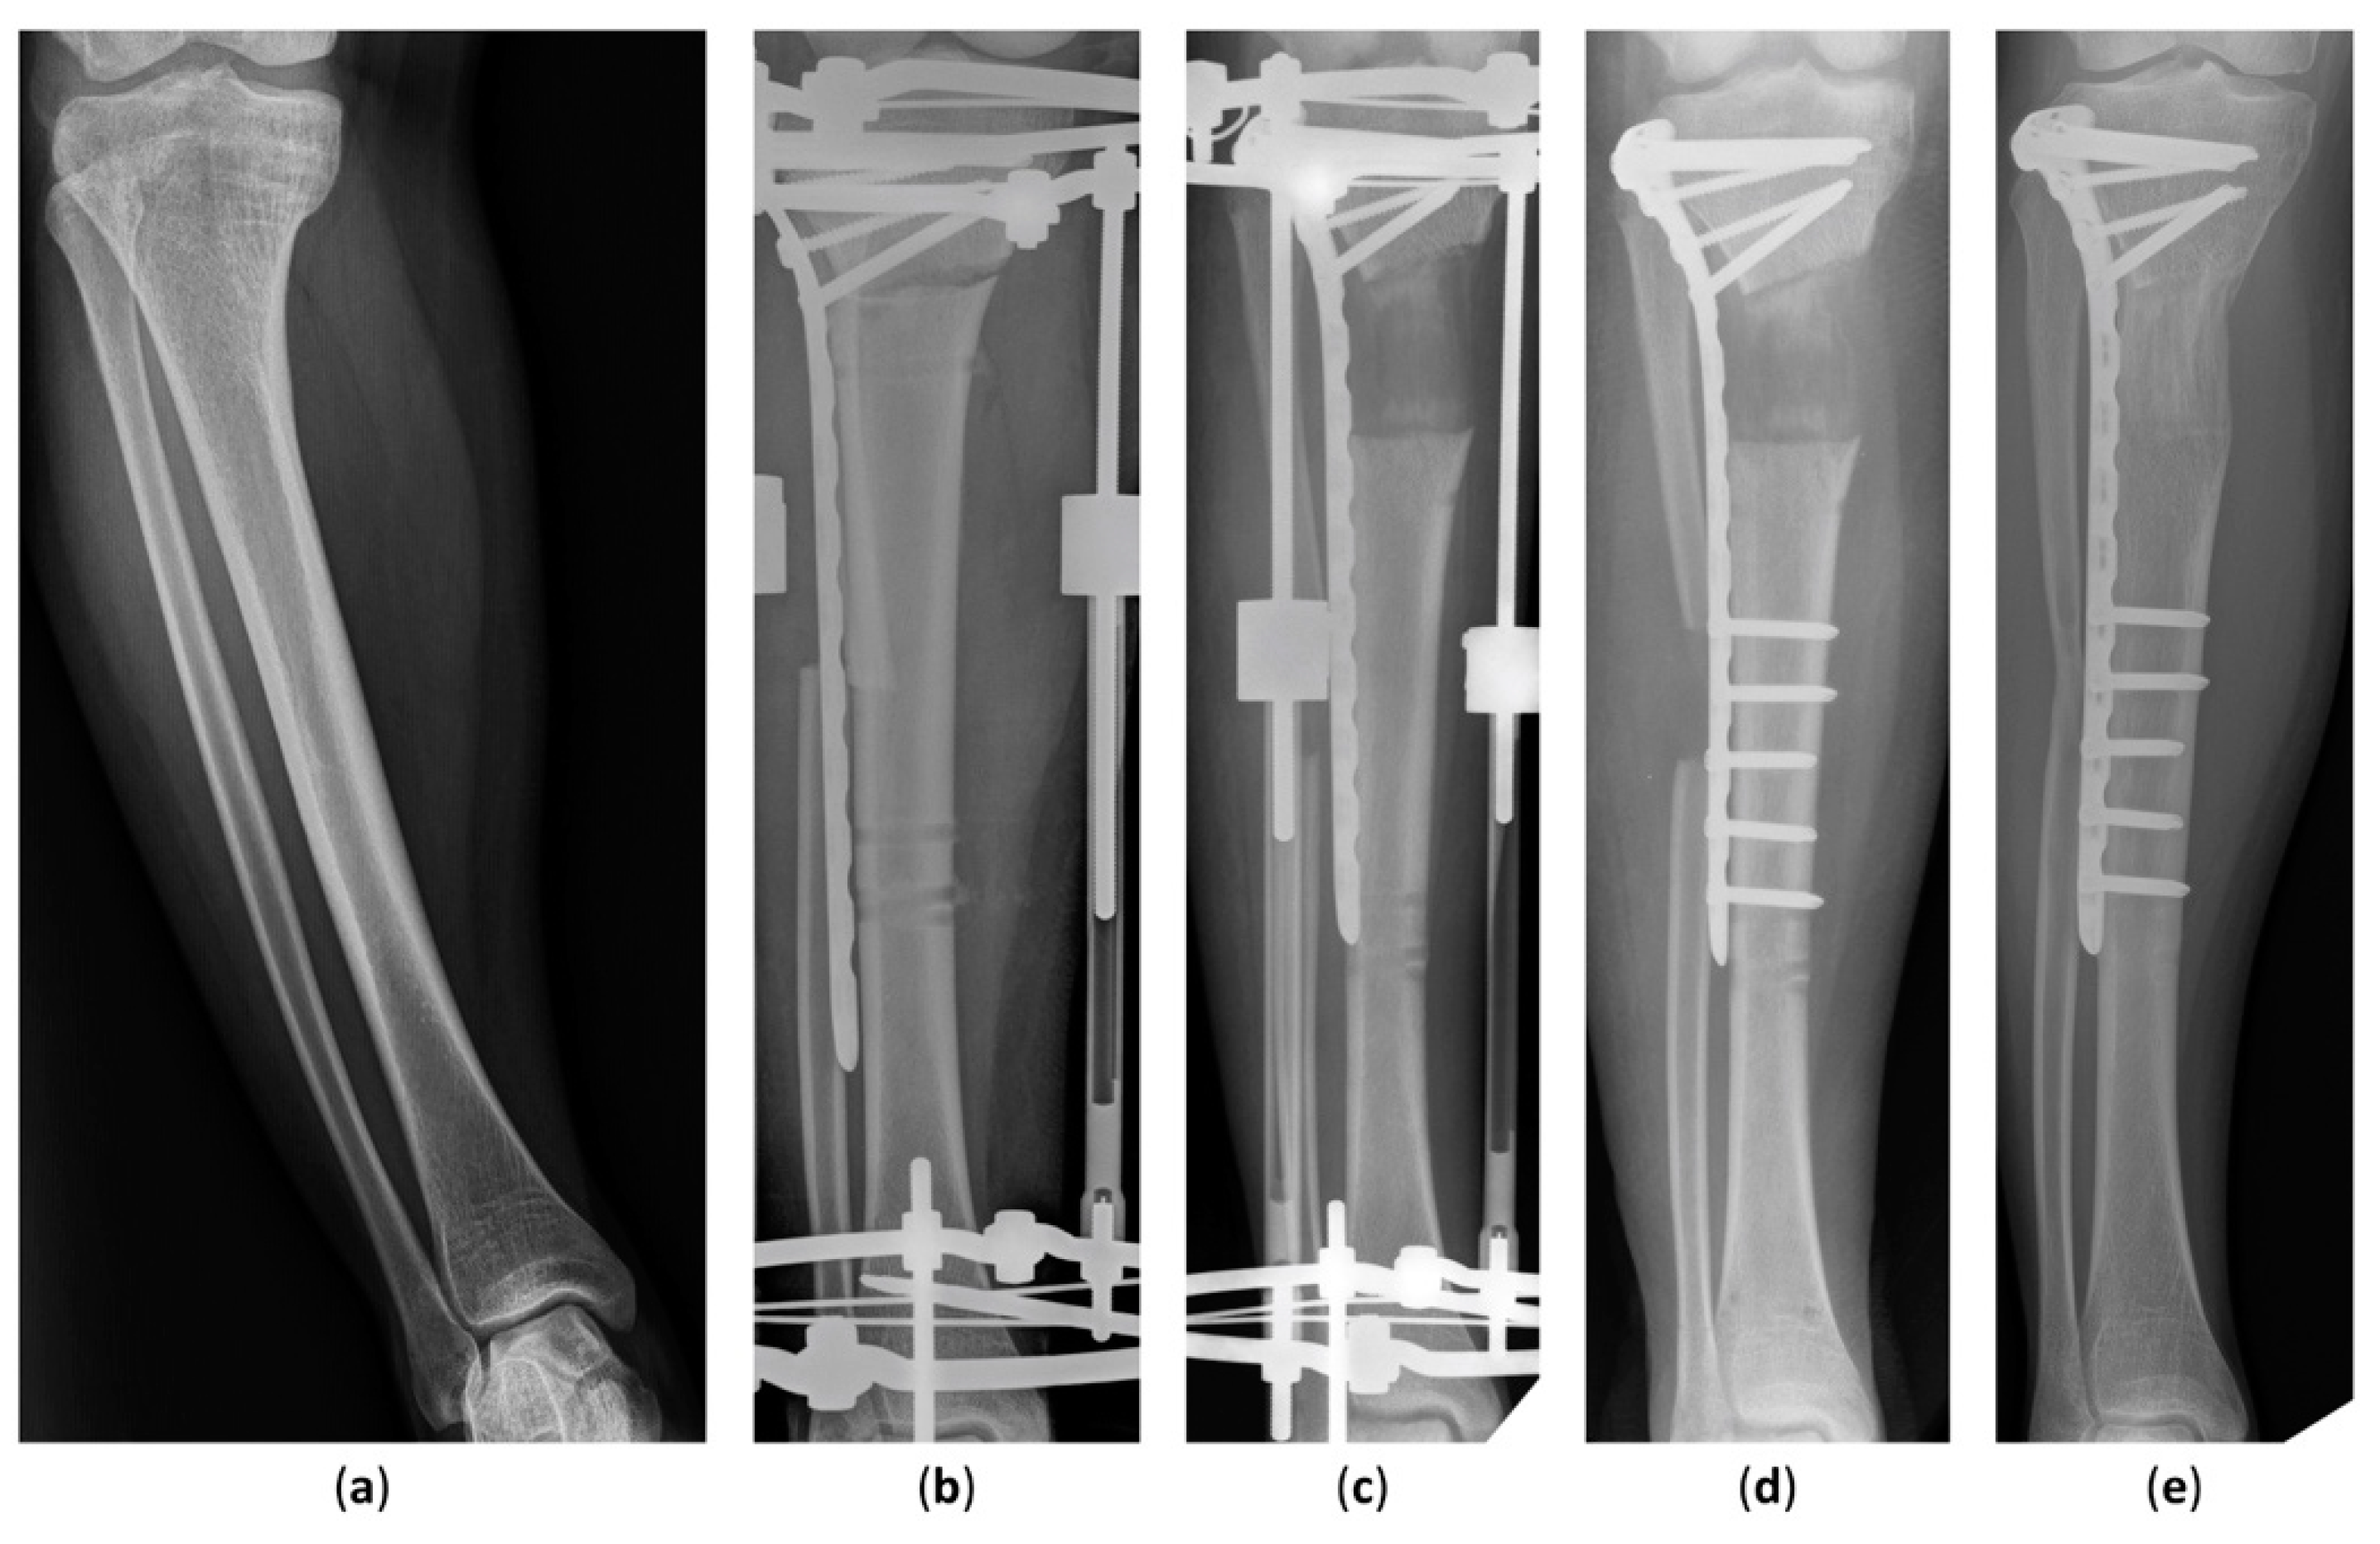

The latest postoperative radiographic measurements including the mLDFA, MPTA, and MAD are summarized in Table 3. The mean postoperative mLDFA was 85.0° (range, 79.5°–91.0°) in Group 1 and 86.5° (range, 80.0°–93.4°) in Group 2. The mean postoperative MPTA was 86.4° (range, 80.2°–93.5°) in Group 1 and 87.6° (range, 81.3°–93.5°) in Group 2. The postoperative MAD, the indicator of lower-limb malalignment, was 14.2 mm (range, 1.0–46.0 mm) in Group 1 and 6.7 mm (range, 3.0–13.0 mm) in Group 2. All in all, the postoperative mLDFA, MPTA, and MAD of Group 1 were not distinguishable from Group 2. The case of an 18-year-old girl with hypophosphatemic rickets who underwent acute angular correction and fixator-assisted lengthening is demonstrated in Figure 2 and Figure 3 at 40 months follow-up.

Figure 2. Anteroposterior radiographs of an 18-year-old girl who underwent fixator-assisted plating and acute angular correction for leg-length discrepancy. (a) A preoperative anteroposterior view of the tibia. (b) The procedure was conducted using an Ilizarov apparatus and a submuscular plate. (c) Satisfactory tibial lengthening and alignment were achieved. (d) The distal part of the submuscular plate was fixed at removal of the external fixator. (e) The distracted callus healing with good consolidation was seen in the latest radiograph 40 months after the operation.